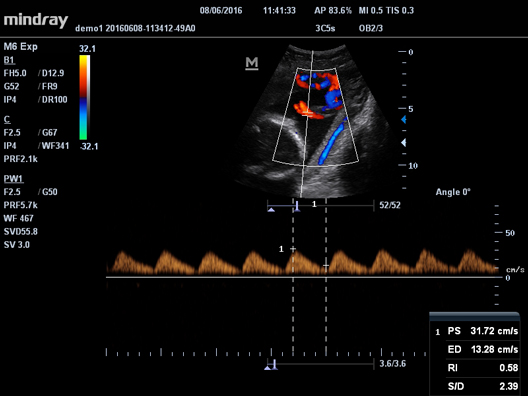

HR Flow

Передовая технология на основе эксклюзивного алгоритма обработки изображений Mindray, обеспечивающая улучшенную визуализацию мельчайших сосудов и сложных структур потока.

Галерея изображений